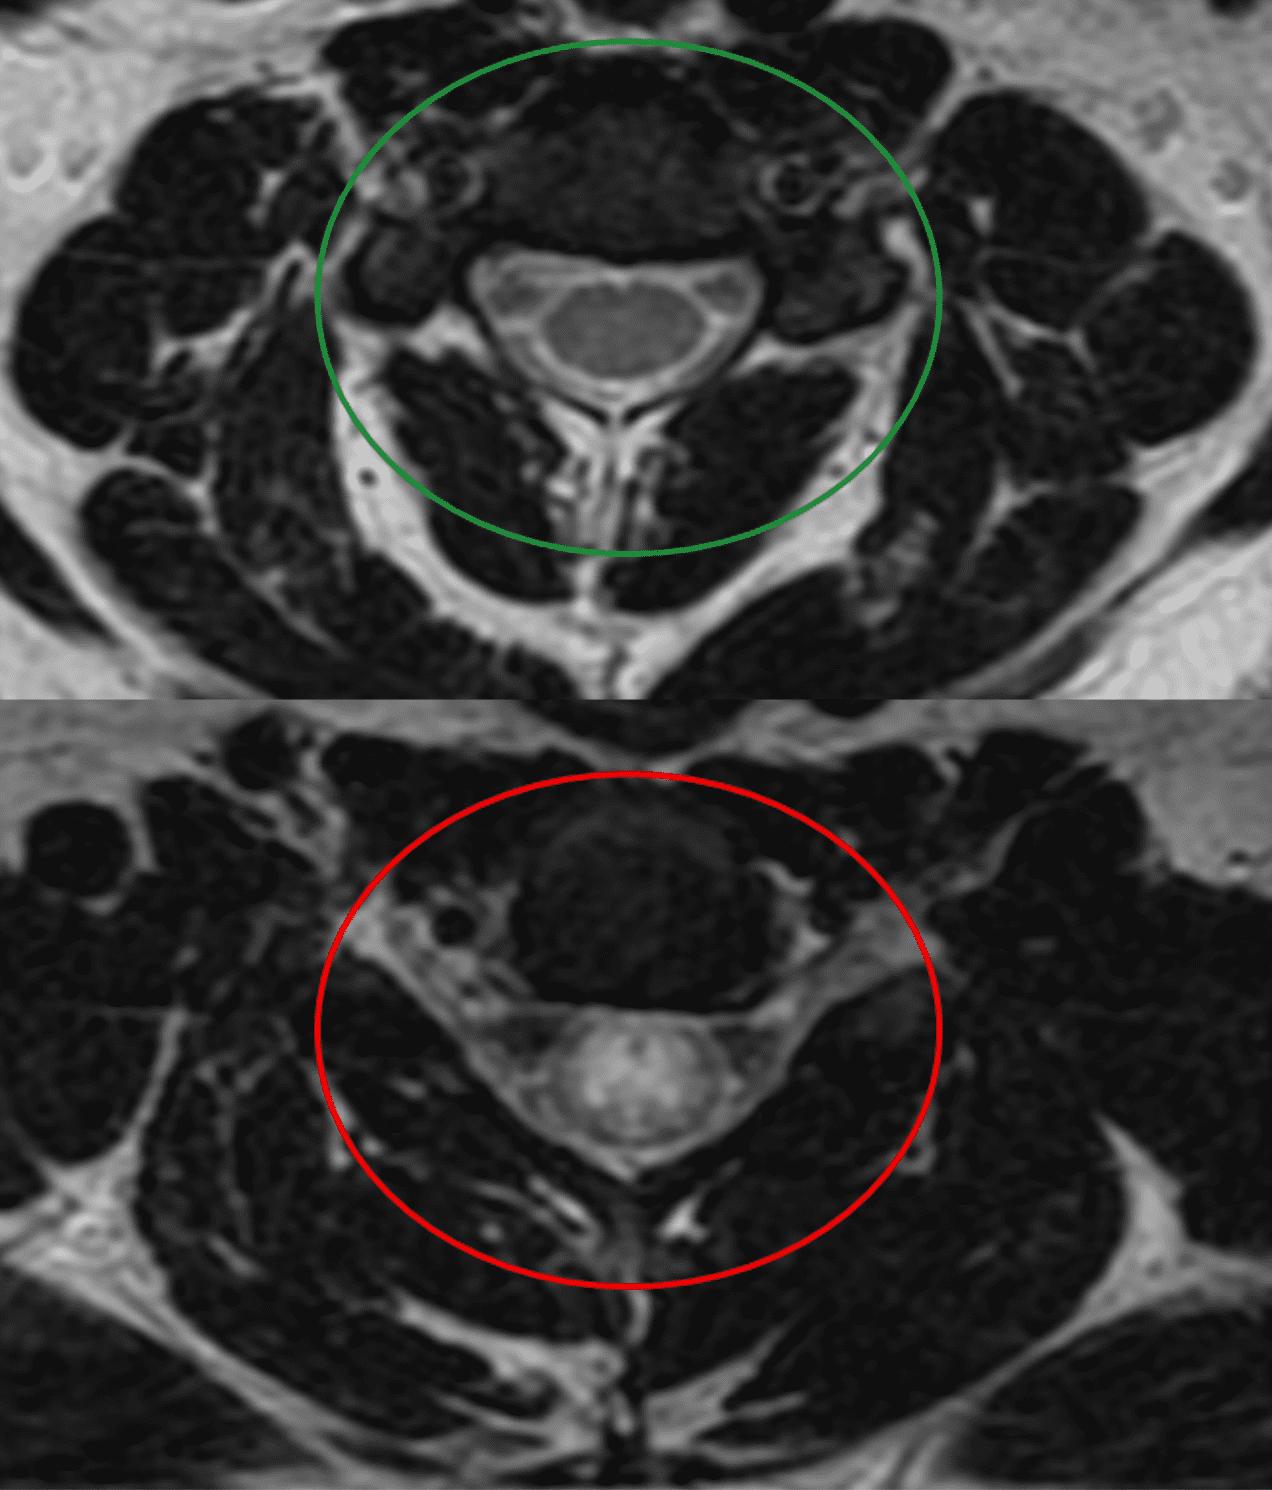

Damien Robinson, a 19-year old resident of Paulding County, Georgia, secured Bell Law Firm to file a medical malpractice action in Dekalb County against WellStar Kennestone Hospital. In March of 2018, two doctors employed by WellStar Medical Group failed to properly diagnose Robinson’s spinal cord injury — treating it instead as a psychiatric problem. The spine injury could have been treated in time but was not treated. The medical failure leaves Damien Robinson with permanent neurological injuries.At 18 years old, Damien Robinson was normally healthy and athletic. Out of nowhere one day, he suffered neurological symptoms including chest pain, weakness, sensory loss and numbness in his feet. Damien’s mother took him to the Emergency Department (ED) at WellStar Kennestone.For a healthy young man, symptoms like these have a short list of potential causes. At the top of the list sits transverse myelitis, a condition causing inflammation along a section of the spinal cord. Doctors can usually treat transverse myelitis simply by giving the patient high-dose steroids for the inflammation. If treated promptly, symptoms from transverse myelitis generally subside, leaving no permanent injury.In fact, Damien did have transverse myelitis. But the WellStar Kennestone doctors did not consider or treat it.The ED doctor ordered the wrong diagnostic test. The ED doctor should have ordered MRI scans of the full spine, with IV contrast. That would have revealed the transverse myelitis. Instead, the ED doctor ordered MRI scans without contrast, which didn’t help.

The ED doctor then consulted a neurologist, Dr. James Armstrong. Dr. Armstrong — along with neurology Physician Assistant Elizabeth Bleakley — also failed to order the necessary MRI with contrast.Instead of investigating and treating the transverse myelitis, Dr. Armstrong diagnosed Damien with conversion disorder. Conversion disorder is a psychiatric problem whereby the brain manufactures what appear to be spinal and neurological symptoms, but which do not arise from physical problems in the spinal cord. Conversion disorder is a residual diagnosis – sometime referred to as a “garbage diagnosis,” because doctors can only resort to a conversion disorder after ruling out all physical (non-psychiatric) causes of the symptoms.Dr. Armstrong and PA Bleakley did not rule out the most obvious potential cause of Damien’s symptoms — transverse myelitis — before resorting to a conversion disorder diagnosis.“To prematurely diagnose someone of conversion disorder is dangerous because it can lead medical providers to abandon investigation and proper treatment of actual physical causes,” states Lloyd Bell. “If an incorrect conversion-disorder diagnosis is made, then a physical problem may remain untreated, leading to unnecessary harm to the patient. That’s exactly what we see here with Damien.”Because of the doctors at WellStar Kennestone, Damien’s transverse myelitis went untreated for days and cost him his chance of a normal or partial recovery.Plaintiff Damien Robinson seeks compensatory damages, as well as damages for medical costs and other damages including physical, economic and emotional injuries.“In this case, both Dr. Armstrong and PA Bleakley failed my client,” comments Bell. “The standard of care required them to investigate whether Robinson suffered from transverse myelitis and to treat him with high dose steroids. They failed to do their job and uphold that standard. I want the public to be aware of the risk of malpractice and misdiagnosis when experiencing neurological symptoms. This improper diagnosis robbed Damien of many able-bodied years, and these health providers should be held accountable.”For more information about Bell Law Firm’s success in helping victims of medical malpractice, visit: www.belllawfirm.com/results.About Bell Law FirmBell Law Firm is Georgia’s preeminent firm for victims of medical malpractice. Founded in 1999 by Lloyd Bell, the firm has recovered more than $100 million for patients and families of people injured or killed due to medical negligence. Bell has more than 25 years of experience in federal and state courts, and he has represented clients in more than 75 jury trials and hundreds of successful settlements. Specializing in litigating misdiagnoses, surgical errors, and other types of malpractice, Bell Law firm differentiates itself with deep legal expertise, a mastery of technology in the courtroom and a compelling manner of storytelling. In 2018, Daily Report, the leading source of legal news in Atlanta, named Bell Law Firm as Personal Injury Litigation Team of the Year.